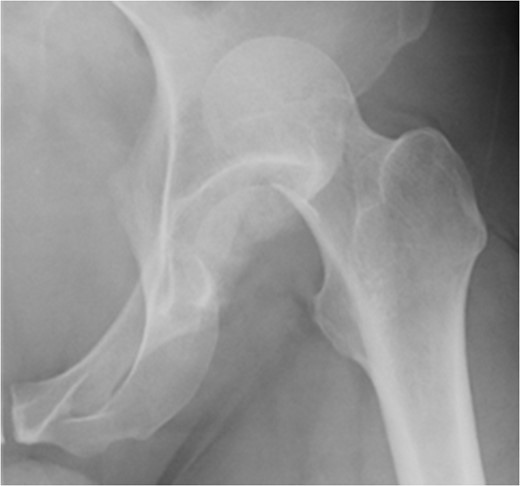

A fit and well man in his 40s had fallen while hiking up a steep hill. He complained of immediate onset, severe left hip pain and inability to move. He was airlifted to our hospital and was found to have shortened externally rotated left leg. Plain X-rays were performed in the emergency department (Fig. 1) identifying isolated fracture–dislocation of the left hip. Computed tomography (CT) was performed while en route to theatre (Figs 2 and 3).

Due to the time involved in the airlift extraction, the hip was dislocated for ~5–6 h. He was attended to by the on-call Consultant Orthopaedic Surgeon, and under general anaesthetic, the hip was reduced with no particular difficulty. The case was referred to the department hip specialist. A further CT scan was performed to assess the position of the fracture to aid in pre-op planning.